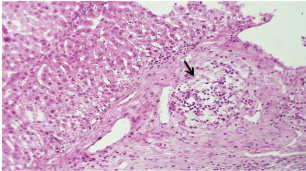

Histopathological examination of rabbits infected with T. annulata (G2) demonstrated progressive pathological alterations in various organs, in contrast to the control group (G1), which exhibited no abnormalities. At 14 days of post-infection, the lungs exhibited moderate alveolar thickening, hyperemia, and the presence of developed schizonts, indicating early tissue involvement (Fig. 4). The liver showed multiple necrotic areas, extensive venous congestion, and parasitized red blood cells, suggesting severe hepatic distress (Fig. 5). The spleen exhibited scattered macrophages containing microschizonts and hemosiderin-laden macrophages, reflecting both immune activation and erythrocyte breakdown (Fig. 6). The kidneys were affected by tubular infiltration with parasitized mononuclear cells (MNCs) (Fig. 7), whereas the mesenteric lymph nodes showed marked architectural disruption and merozoite aggregation (Fig. 8), suggesting significant immune system involvement.

Fig. 4. A histopathological section of lung of (G2) at 14 days postinfection showing moderate thickening of alveolar tissue with presence number of developed schizonts accompanied by alveolar hyperemia (H&E stain X 40).

Fig. 6. A histopathological section of the spleen of (G2) at 14 days postinfection shows the scattered presence of macrophages containing micro-schizont (black arrow) and hemosiderin laden macrophages (red arrow) (H&E stain X 40).

Fig. 8. A histopathological section of mesenteric lymph node of (G2) at 14 days postinfection showing marked disruption of the lymph node architecture (red arrow) with evidence of merozoites aggregation (black arrow) (H&E stain X 40).